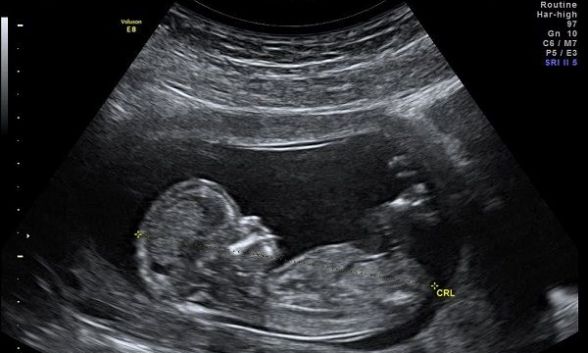

Según un portavoz del Gobierno, las mujeres que busquen abortos médicos podrán tomar píldoras abortivas (mifepristona y misoprostol) en el hogar hasta la décima semana de embarazo. Los médicos envían las píldoras por correo al paciente después de consultar con ellas por teléfono o un enlace de video.